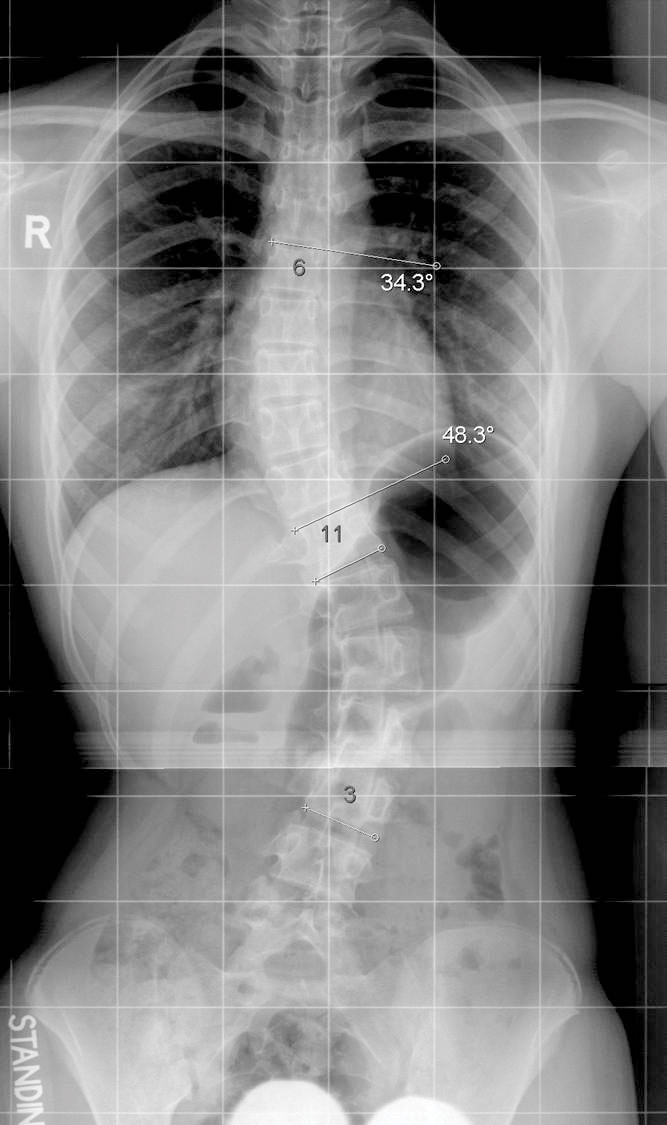

脊柱側彎 — 遺傳因子惹的禍?

每年均有不少學童,在衛生署提供的學童健康服務(俗稱學童保健)中,檢查出懷疑患有脊柱側彎。有醫學教授指出,脊柱側彎的成因與遺傳因子有關,不一定是姿勢不良引起。因此家長了解子女患上此症的真正成因,才可「對症下藥」。 …繼續閱讀